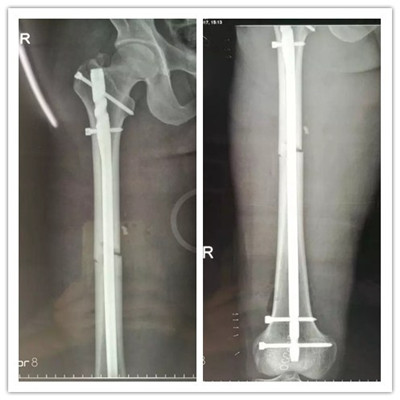

經(jīng)過(guò)慎重考慮和周密的術(shù)前計(jì)劃,羅軍主任帶領(lǐng)帶領(lǐng)科室團(tuán)隊(duì)用骨折閉合復(fù)位髓內(nèi)釘固定的微創(chuàng)方法為患者進(jìn)行手術(shù)。 近90分鐘的精心手術(shù),骨折處沒(méi)有切開(kāi),采用間接復(fù)位的方法就使骨折塊達(dá)到了解剖復(fù)位,并用微創(chuàng)切口導(dǎo)入髓內(nèi)釘對(duì)骨折進(jìn)行了牢固的固定,圍手術(shù)期沒(méi)有輸血,醫(yī)療費(fèi)用也明顯降低。

▲骨折的完美復(fù)位和內(nèi)固定